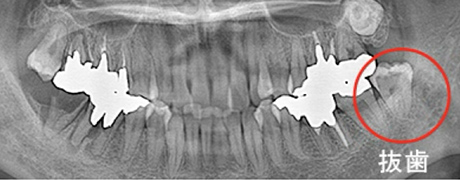

親知らずの抜歯

(難抜歯対応可能)

大人の歯が、歯ぐきや歯槽骨の中に埋まっている状態が埋伏歯と呼ばれます。必要があれば、歯茎を切開して歯を取り出します。埋伏歯の周りの神経や血管の位置によっては、一般的な抜歯と比べはるかに高い技術が要求されます。

親知らずの難症のケース

治療症例